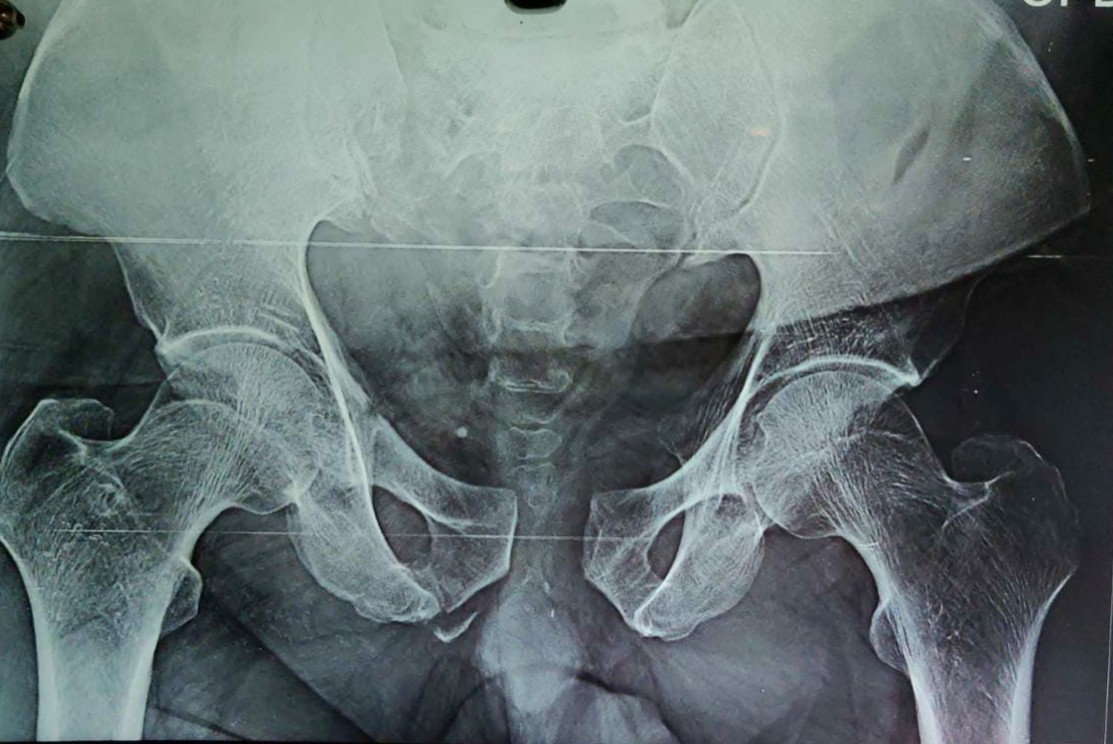

A 50-year-old male was admitted following a fall from a height of approximately 10 feet at a construction site, resulting in spine and pelvic fractures. He initially received care at a local hospital for hemorrhagic shock before being transferred to our tertiary care center via air ambulance 2 days later. On arrival, the patient was conscious but remained hemodynamically unstable due to hypovolemic shock, which was managed in the intensive care unit (ICU). A thorough evaluation, including scans, revealed multiple injuries: A right sacral ala fracture, D6 and L1 burst fractures, right transverse process fractures of several lumbar vertebrae, pubic diastasis with a right anterior column fracture, as well as fractures of the right medial clavicle and the right seventh rib (Fig. 1).

Figure 1: Right sacral ala fracture (Dennis type 2) and pubic diastasis with right anterior column fracture.